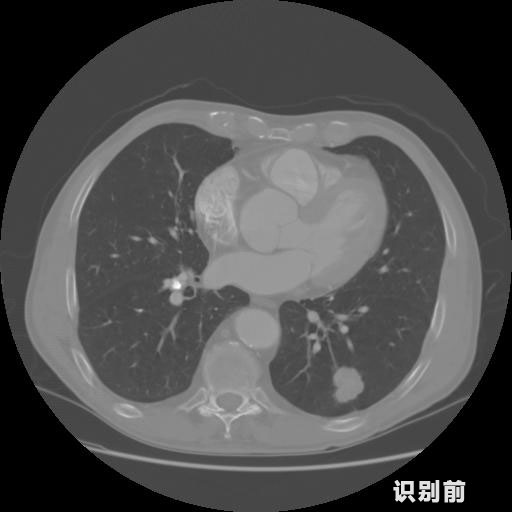

英特健康A(chǔ)I深度學習醫(yī)療圖像識別系統(tǒng)案例_胸部CT

1.發(fā)現(xiàn)肺結(jié)節(jié)的可能性為95.56%---位于框指數(shù)位置:[331.70554 366.13406 365.21707 403.96234]